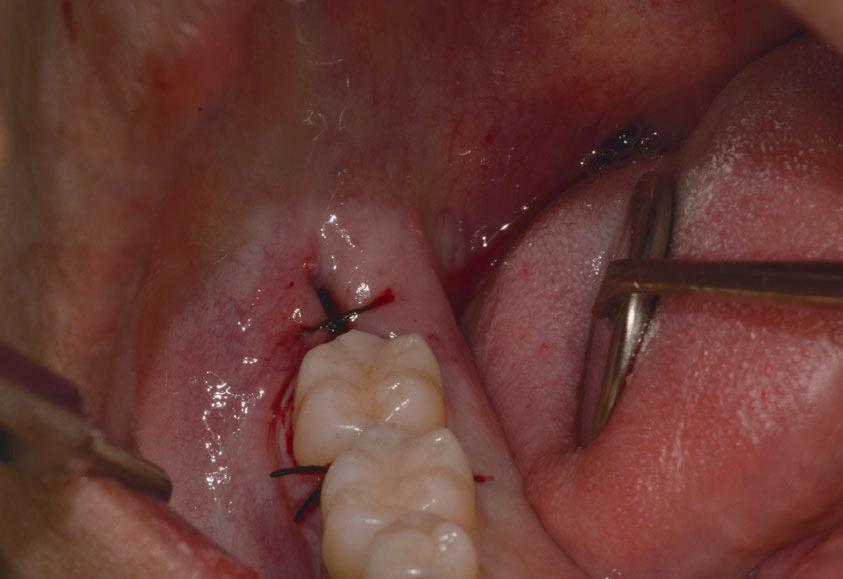

Questo è un paziente di 22 anni ed essendo un amico, ho potuto ben documentare il caso con il suo consenso: il suo dente del giudizio inferiore sinistro è stato estratto utilizzando il manipolo dritto. Figg. 143-149

Figg. 143-149 - Caso 1, paziente di 22 anni: tecnica di estrazione con divisione orizzontale utilizzando il manipolo dritto. Fig. 143 Fig. 144 Fig. 145 Fig. 146 Fig. 147 Fig. 148 Fig. 149

In generale l’estrazione di un dente del giudizio inferiore, utilizzando il manipolo dritto, richiede un’incisione posteriormente alla superficie mesiale del secondo molare. Se il dente non è incluso, la rimozione di osso vestibolare non è necessaria, ma al contrario, più il dente è in profondità e più osso vestibolare dovrà essere rimosso. Una volta che l’osso vestibolare è stato rimosso, il dente viene sezionato vestibolo-lingualmente e separato in una metà mesiale e una distale, utilizzando una leva. Il segmento distale del dente che non giace nel sottosquadro della regione distale del secondo molare viene rimosso per primo e poi viene rimosso quello mesiale. Figg. 150-156